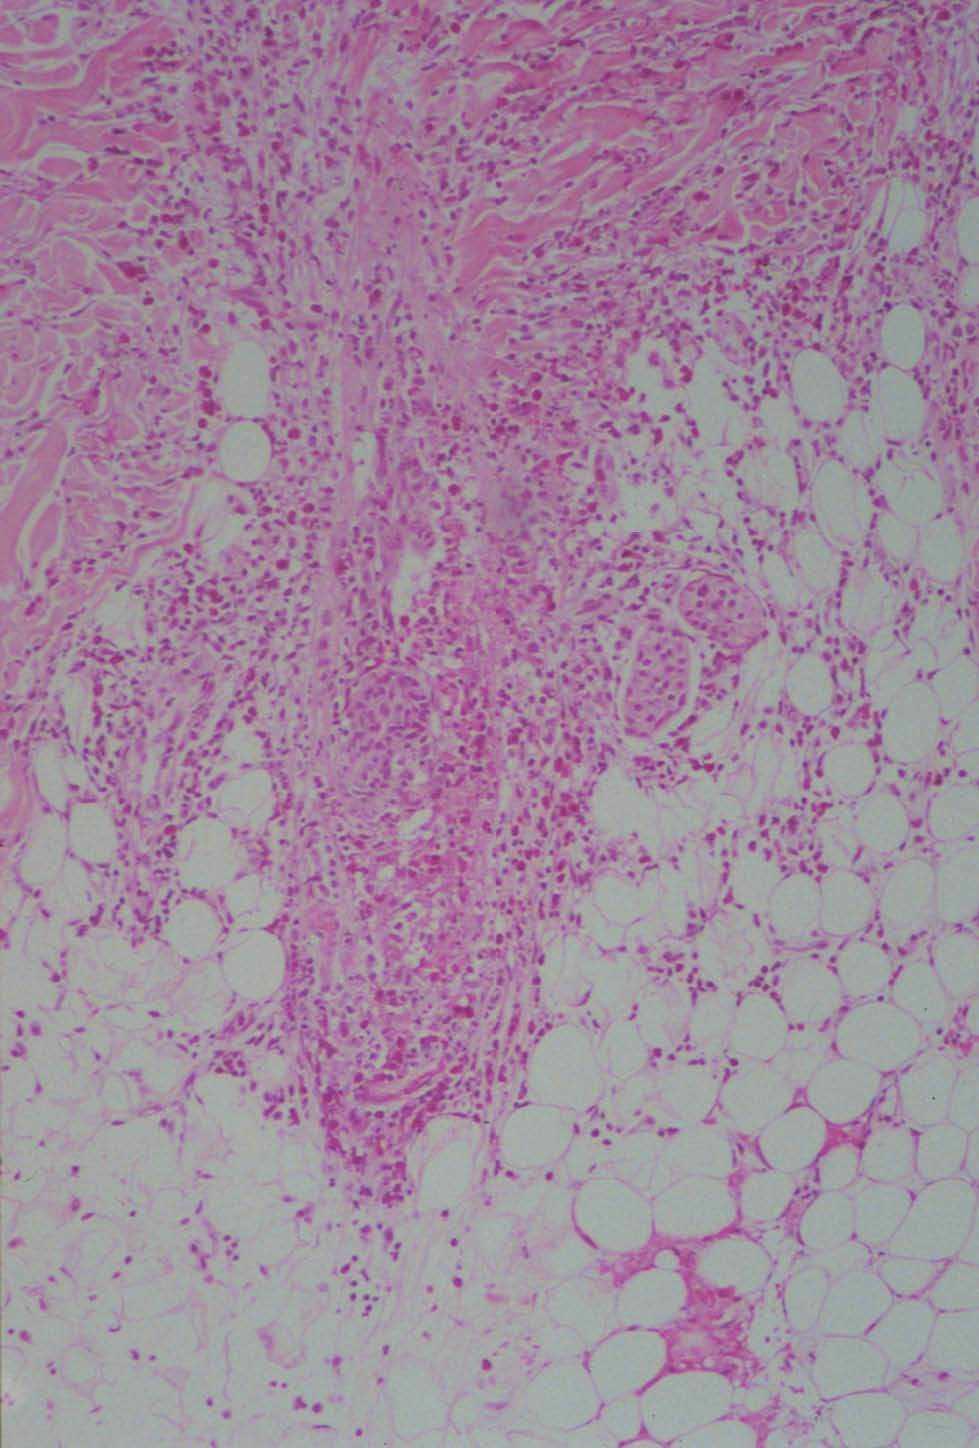

En el estudio histológico podía observarse un moderado infiltrado inflamatorio polimorfo compuesto por polimorfonucleares, eosinófilos y linfocitos, alrededor de los vasos y en el intersticio. Algunos de los folículos se encontraban densamente infiltrados por polimorfonucleares y eosinófilos, que destruían parcialmente la pared, ocupando el infundíbulo y afectando también la glándula sebácea (figs. 2 y 3). Se realizaron tinciones para la detección de estructuras micóticas (PAS y plata-metenamina) que resultaron negativas.

Fig. 3.--Infiltrado inflamatorio eosinofílico de dermis e hipodermis. (Hematoxilina-eosina, x40.)